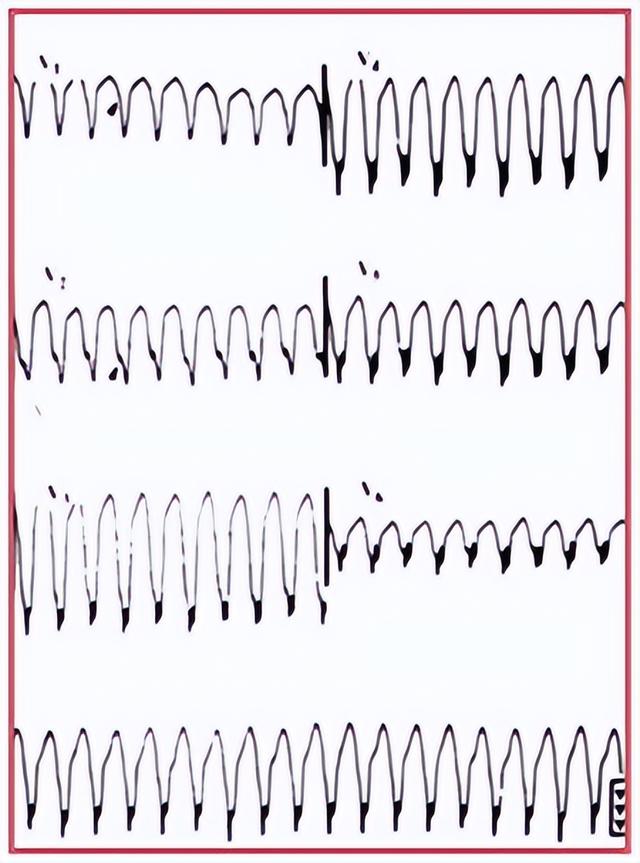

对于节律完全不规整的宽QRS心动过速,首先需要排除房颤伴预激的可能。房颤伴旁路前传的心电图有3项特征性表现,即“快”、“宽”、“乱”。“快”指心室率极快,多>220bpm;“宽”指QRS的宽度更宽,多>140ms;“乱”指心室率绝对不整齐,出现“手风琴现象”。

“手风琴现象”: 房颤合并预激综合征(旁路前传)

PSVT心律绝对规则,VT心律略不齐。